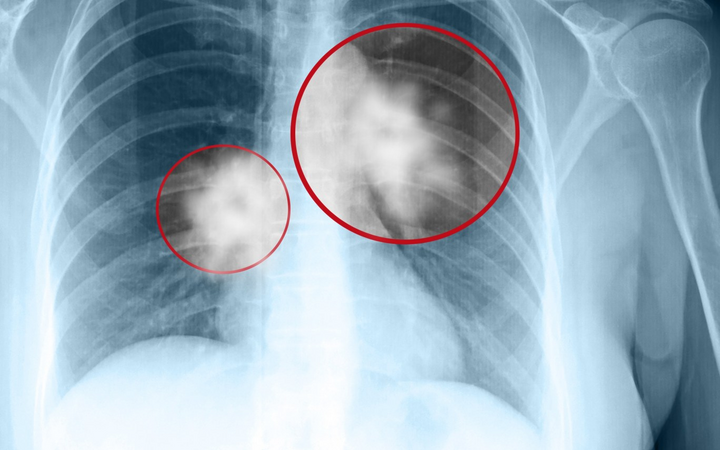

Ung thư phổi khi còn ở giai đoạn đầu thường ít khi có triệu chứng điển hình, dưới đây là 9 dấu hiệu ung thư phổi giai đoạn đầu để bạn cảnh giác và đi khám ngay.

Bài viết trên website Bệnh viện Đa khoa Tâm Anh có sự tư vấn chuyên môn của GS.TS.BS. Ngô Quý Châu cho biết, ung thư phổi (tiếng Anh là Lung Cancer) là loại ung thư khởi phát từ phổi hay còn được gọi là khối u ác tính ở đường hô hấp. Bệnh xảy ra khi một khối u ác tính hình thành trong phổi, phát triển nhanh về kích cỡ dẫn tới xâm lấn, chèn ép các cơ quan xung quanh. Hai lá phổi trong lồng ngực có chức năng hấp thụ oxy khi hít vào và thải carbon dioxide (CO2) khi thở ra.

Ngoài ra, vẫn có trường hợp có thể xuất hiện các khối u phổi lành tính. U lành có về cơ bản có sự khác biệt rất lớn với u ác tính (tế bào ung thư). Tuy nhiên, để xác định chính xác tính chất của khối u, vẫn cần các phương pháp chẩn đoán khoa học và chính xác từ các bác sĩ, chuyên gia y tế.